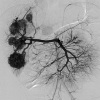

Эмболизация гемангиомы печени

Эмболизация гемангиомы печени - это безоперационный способ удаления сосудистой опухоли, расположенной в паренхиме органа. Гемангиомы печени часто бывают множественными, что значительно усложняет перспективы их хирургического лечения. Во время ангиографии выявляются дополнительные ветви печеночной артерии, кровоснабжающие гемангиому. В их просвет вводят эмболизирующий агент, что приводит к полному прекращению кровотока в опухоли. Эмболизация может быть выполнена как заключительная процедура или как подготовка к последующей энуклеации опухоли или резекции печени. Стоимость зависит от технических особенностей процедуры.